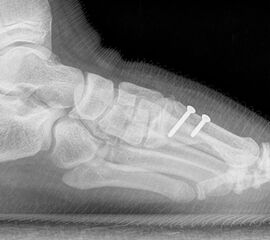

Operative Therapie

Ob es eine untere Altersgrenze für einen operativen Eingriff beim juvenilen Hallux valgus gibt, wird kontrovers diskutiert. Es gibt Autoren, die empfehlen aufgrund eines zu befürch­tenden Rezidivs den Schluss der Wachtumsfugen abzuwarten 1112, für andere gibt es beim Vorliegen von Beschwerden keinen Grund auch schon früh und damit wachstums­lenkend einzugreifen 1314.

Bezüglich der Operationstechniken wird von früher häufig durchgeführten alleinigen Weich­teileingriffen am Großzehengrundgelenk aufgrund hoher Rezidivraten abgeraten 15. Die Operation nach Mc Bride mit lateralem Release, Exzision des lateralen Sesambeins, Abtragen der Pseudoexostose, Sehnenetransfer des M. adductor hallucis und mediale Kapselraffung zeigte unbefriedigende Mittel- und Langzeitergebnisse 16. Die Cerclage fibreux (mediale Kapselraffung) und das laterale Kapselrelease wird heute in Kombination mit einem knöchernen Eingriff angewendet. Bezüglich des Einsatzes von minimalinvasiven Operations­techniken vor Wachstumsabschluss liegen bisher keine Daten vor. Alle Osteotomien lassen sich nach Bedarf miteinander kombinieren. Es ist darauf zu achten, dass Osteotomien keine offenen Wachstumsfugen verletzen.

• Medial zuklappende Grundphalanxosteotomie nach Akin 17

• Subcapitale distale Chevron Osteotomie nach Austin 18

• Diaphysäre Osteotomie

• Scarf 19

• Ludloff 20

• Proximale Metatarsale I Osteotomien 21

• medial aufklappend – verlängernd

• lateral zuklappend – verkürzend

• bogenförmige Crescentic Osteotomie

• proximale Chevron Osteotomie

• proximale Verschiebeosteotomie

• medial aufklappende Cuneiforme I Osteotomie 1522

• Wachstumslenkung: Hemiepiphysiodese der lateralen Basisfuge am Metatarsale I  23

• Nach Schluss der Wachstumsfugen: TMT I Arthrodese nach Lapidus 2425